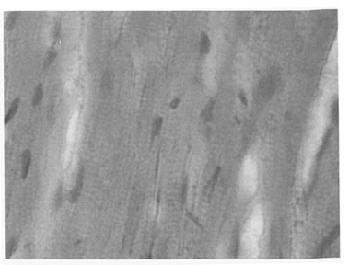

Рис. 2. Очаги фуксинофилии, красно-оранжевые мышечные волокна.

В таких участках фуксинофилия приобретает гомогенный, а в отдельных мышечных волокнах зернистый характер. Подвергшиеся выше перечисленные изменения мышечных волокон, слабо поглощают фуксин и при окраске методом Селье приобретают красно-оранжевый оттенок. Метод Селье достаточно избирательно отображает состояние сократительного аппарата кардиомиоцитов.

При окраске толуидиновым синим выявляются очаги метахромазии. Электронно-микроскопическое исследование кардиомиоцитов при ранней (24 часа) стадии краш-синдрома после одночасового раздав-ливания выявило картину вакуольной дистрофии. Ядра приобретают лопастную форму, хроматин занимает краевое расположение. Митохондрии отечные, набухшие с просветленным матриксом, деструктуризацией (уменьшением количества) крист, гомогенизацией.

Проводящая система характеризуется сильно сокращенными миофибриллами. В некоторых клетках выявляется разрушение сарколеммы и выход внутриклеточного содержимого в межклеточное интерстициальное пространство. Наблюдается всеобщее уплотнение хроматина, встречается при кариопикнозе и кариорексисе. Наблюдается деструктуризация клеток проводящей системы и просветление цитоплазмы матрикса. Вышеизложенное свидетельствует о расстройствах энергетического обмена, глубоких нарушениях структурной организации клеток проводящей системы, преимущественно синусового узла.